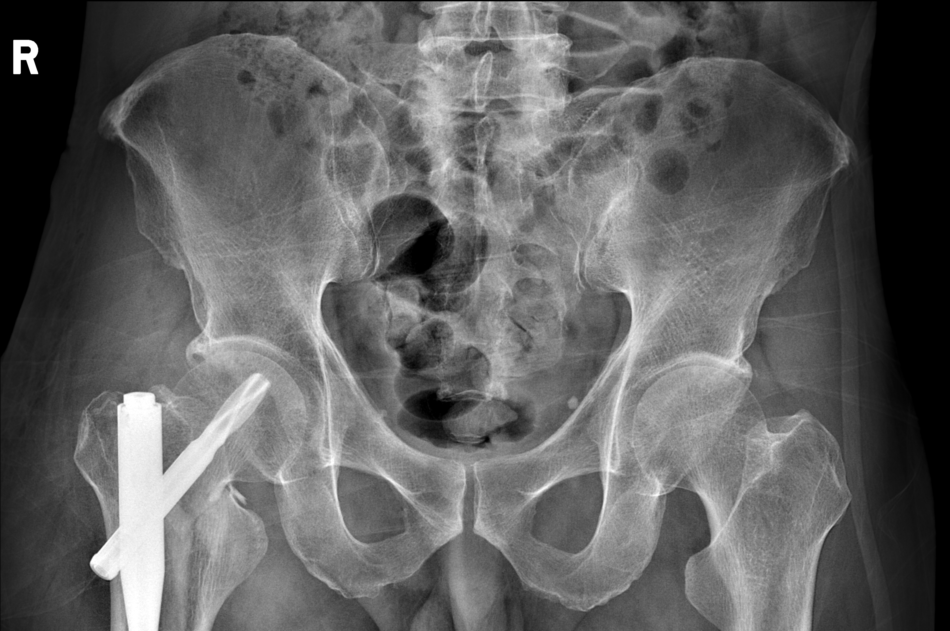

5.辅助检查:我院骨盆CT示:右侧股骨颈及转子间骨折。

术前影像学检查: